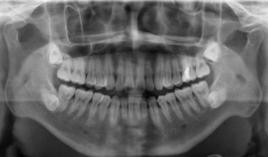

牙鮃其面積為3×4平方厘米。一張牙片可以顯示3-4個牙齒。牙齒在牙片上顯示出白色阻射影像。其中牙釉質阻射最強,牙本質和牙骨質阻射低於牙釉質。牙髓腔呈黑色透明影像,根管口至根尖孔呈逐漸變細的影像。

牙片是口腔科套用最廣的檢查手段,也是最常用的,因為它在牙的治療前、治療中和治療後都有助於診斷和治療。治療前有助於發現病變;治療中可用插針照相方法了解擴根情況等;治療後觀察療效等。臨床上,利用牙片對牙齒硬組織病變、牙髓病變、尖周病變及牙周病進行診斷治療。